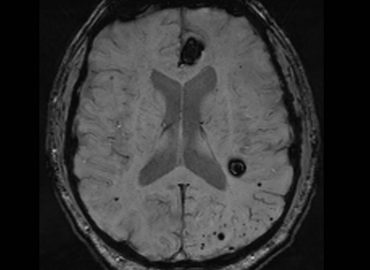

Hombre de 55 años, con antecedentes de cardiopatía y FA, consulta por sindrome convulsivo.